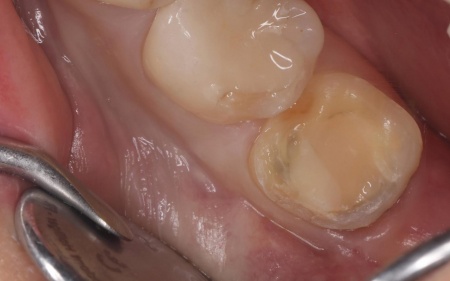

治療中